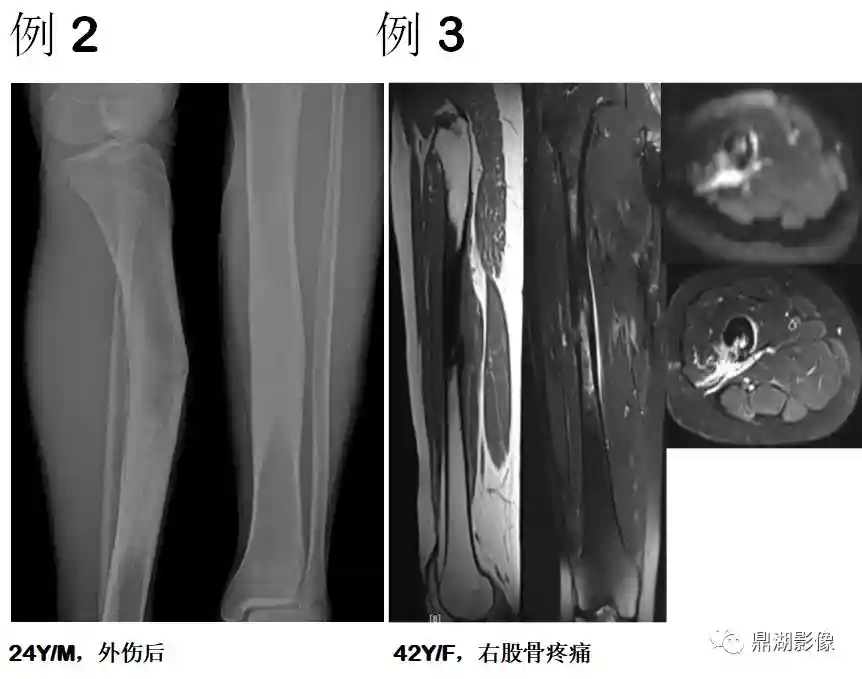

非骨化性纤维瘤

由纤维组织构成,无成骨,并为骨壳所包绕,周围骨组织反应性增生

5-20岁常见,好发于四肢长骨,以胫骨、股骨最为多见

多在外伤后发现,少数表现为局部疼痛

干骺端偏骨干侧,轻度膨胀多房病变;病灶长轴与骨干一致;无骨化